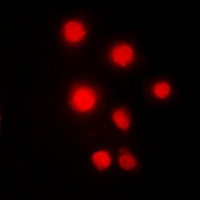

Immunofluorescent analysis of HMGB2 staining in Hela cells. Formalin-fixed cells were permeabilized with 0.1% Triton X-100 in TBS for 5-10 minutes and blocked with 3% BSA-PBS for 30 minutes at room temperature. Cells were probed with the primary antibody in 3% BSA-PBS and incubated overnight at 4 °C in a hidified chamber. Cells were washed with PBST and incubated with a DyLight 594-conjugated secondary antibody (red) in PBS at room temperature in the dark.